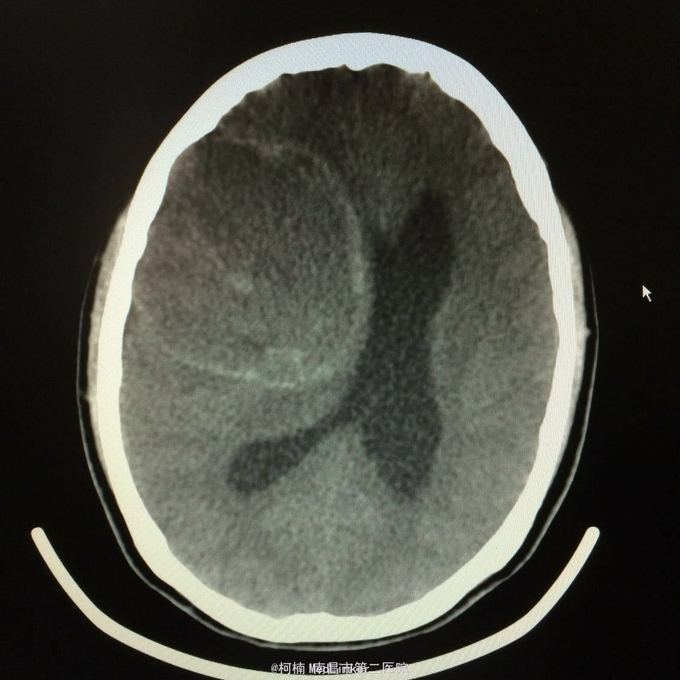

主诉:头痛2年,加重2月 病史:2年前无明显诱因出现头痛,主要为右侧额颞叶胀痛,近两个月来上述症状加重,遂至当地医院行头颅CT提示:右侧额颞叶类圆形异常信号,考虑脑膜瘤合并出血。

神经系统查体阴性 辅助检查:头颅CT提示右侧额颞骨板下肿物伴瘤卒中考虑脑外源性脑膜瘤

右侧额颞脑膜瘤 处理:全麻下行右侧额颞叶占位性病变切除术,术后病理提示:血管型脑膜瘤,WHO1级